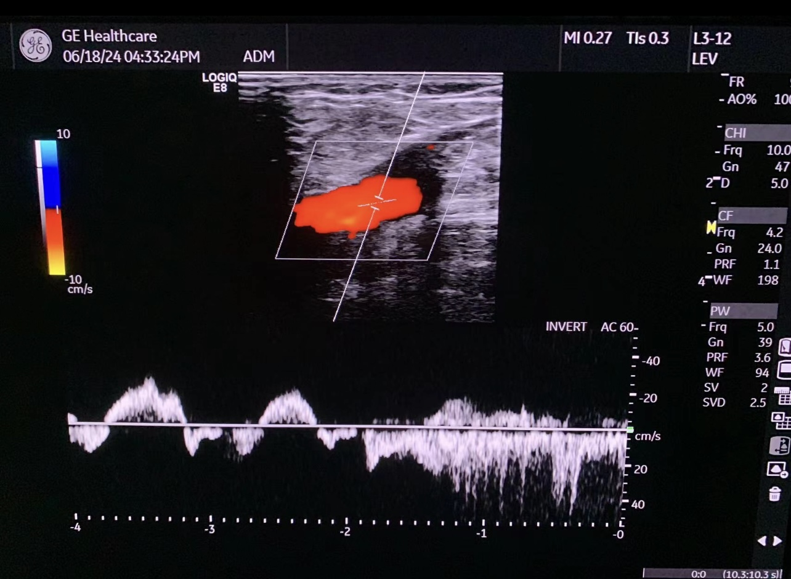

国内首例MOCA手术

2025年8月8日,浙江省人民医院完成了我国第一例MOCA手术。患者为90余岁高龄,心脏功能差,大隐静脉主干表浅,不适合热消融。术中通过4F鞘高速旋转破坏内膜后注入硬化剂,效果理想。